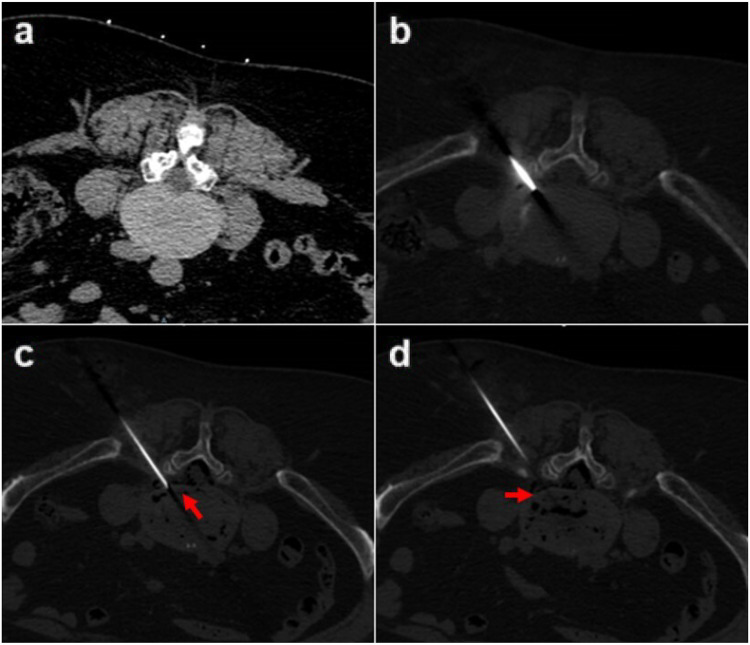

Methods: From January 2019 to December 2020, 60 patients who had LDH with grade I degenerative spondylolisthesis were divided into two groups. Group A adopted TELD while Group B adopted CN combined with CCNL. The surgical efficacy was evaluated according to the visual analogue scale (VAS), oswestry disability index (ODI), quality of recovery-15 (QoR-15), and modified MacNab criteria. Imaging findings including lumbar lordosis (LL), segmental lordosis angle (SL), slip percentage (SP), and disc height (DH) were compared between the two groups pre-operation and at the last follow-up.